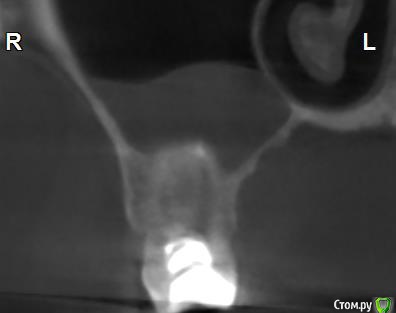

Здравствуйте! Верхний правый шестой зуб пломбировали 3 месяца назад. Примерно месяц назад он начал ныть, после насморка, сначала периодами, а теперь почти постоянно. При постукивание (ощущается не совсем так, как другие зубы) и пальпации десны он не болит. 2,5 месяца назад удаляли кисту из гайморовой пазухи. Может ли быть это какое-то воспаление и есть ли вероятность устранить его какими-нибудь антибиотиками, если да, то как, или может удалить зуб? Если есть воспаление, то какие могут быть последствия если не удалить зуб?

(Снимки с КТ, первые 8(Image) - сделаны сейчас,по 4 в разных проекциях, вторые 8(Before) - сделаны 5 месяцев назад до удаление кисты и повторного пломбирование зуба( до повторного пломбирование он реагировал на горячее, был запломбирован 3 года))